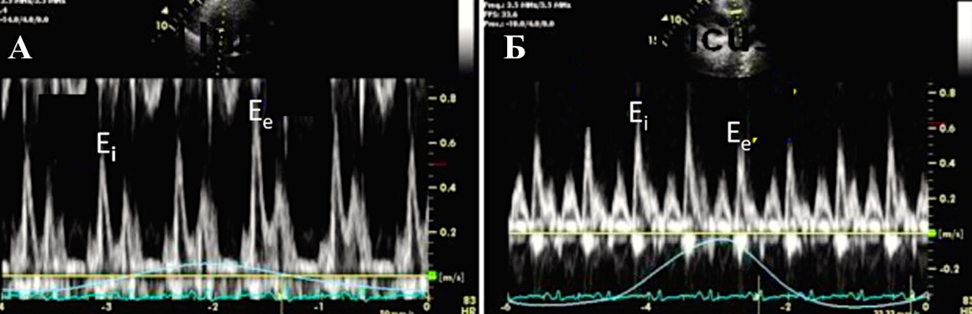

При констриктивном перикардите имеется значительная зависимость профиля кровотока через митральный и трикуспидальный клапаны от фаз дыхания:

- по данным импульсно-волновой допплерографии, в начале вдоха максимальная скорость трансмитрального пика E уменьшается на ≥25%;

- в начале выдоха максимальная скорость транстрикуспидального пика E уменьшается на ≥40% (Приложение А3, рис. А3-1) [116].

В диагностике констриктивного перикардита также может быть полезна тканевая допплерография, демонстрирующая так называемый феномен “annulus reversus”, заключающийся в том, что нормальная или повышенная ранняя диастолическая скорость движения медиальной части митрального кольца (медиальная е') оказывается выше, чем ранняя диастолическая скорость движения латеральной части фиброзного кольца (латеральная е’) (Приложение А3, рис. А3-2) [117].

Сочетание разнонаправленного смещения МЖП в зависимости от фаз дыхания с увеличением ранней диастолической скорости движения медиальной части митрального кольца (медиальная е') ≥9 см/сек имеет самую высокую диагностическую чувствительность (87%) и специфичность (91%) [118].